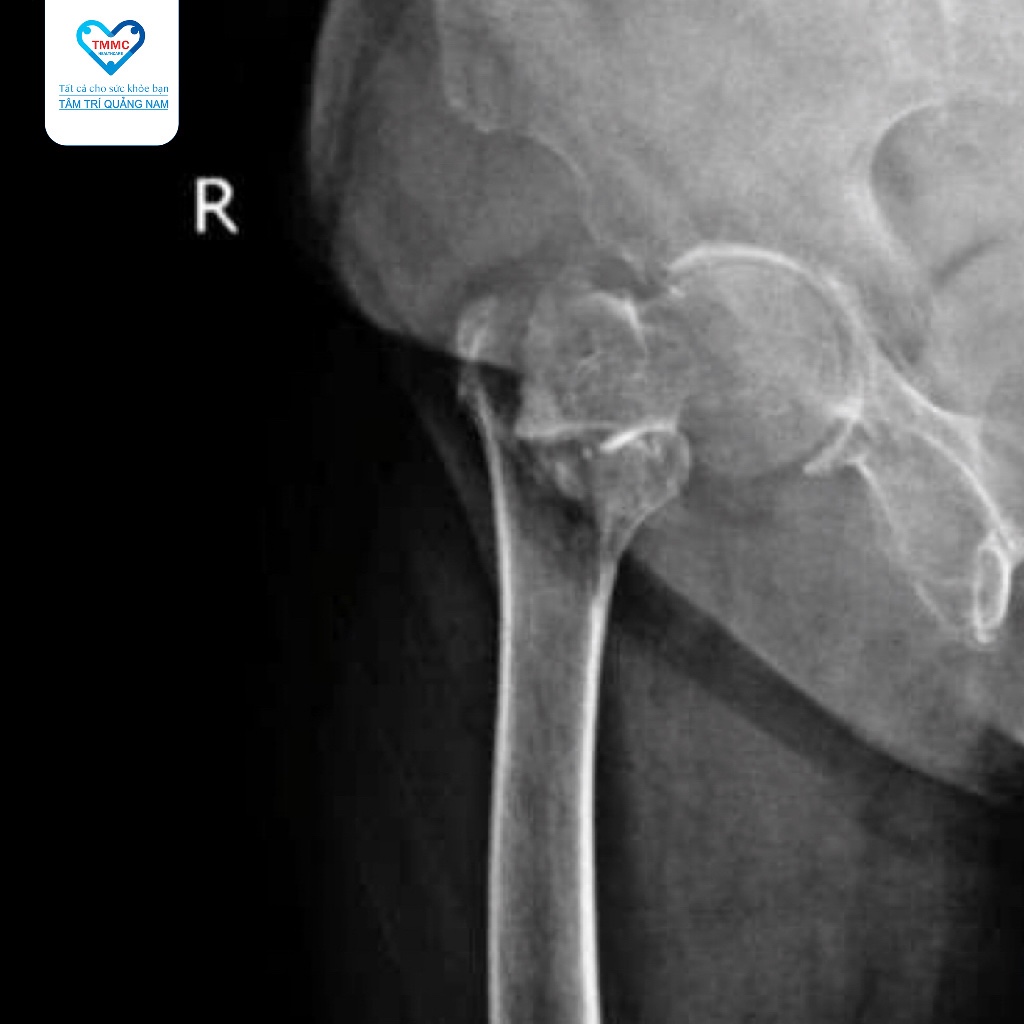

Ngay sau khi nhập viện, bệnh nhân đã được các bác sĩ tiến hành thăm khám lâm sàng và chỉ định chụp phim X-quang, kết quả cho thấy bệnh nhân bị gãy kín phức tạp liên mấu chuyển xương đùi phải, một chấn thương nghiêm trọng thường gặp ở người lớn tuổi hoặc người có bệnh lý nền xương khớp.

Ekip phẫu thuật do BS.CKI Nguyễn Minh Lâm - Trưởng Khoa Ngoại Chấn thương thực hiện đã lựa chọn với phương pháp phẫu thuật kết hợp xương gãy liên mấu chuyển xương đùi bằng đinh nội tủy PFNA, phương pháp tốt nhất hiện nay trong điều trị gãy liên mấu chuyển xương đùi, giúp cố định xương chắc chắn, hỗ trợ quá trình liền xương và phục hồi chức năng vận động sau này.